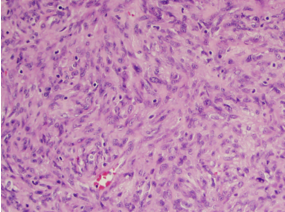

A 53-year old male was referred to the general surgery clinic for a bulge in his right groin. He denied past medical history, and his past surgical history was only significant for an appendectomy. Physical exam revealed a reducible right inguinal hernia in addition to a small left inguinal hernia. An open bilateral inguinal hernia repair with plug and patch mesh was performed electively. At the time of surgery, a nodule was noted in the right hernia sac and the sac with the nodule was subsequently sent to pathology. The final pathology report revealed a GIST on immune histo chemical staining for c-kit, with a high mitotic rate of 7 in a 50 high powered field (Figure 1).

Figure 1 Mixed spindle cells with foci of epitheliod tissues. Mitotic rate of 7/50 HPF.